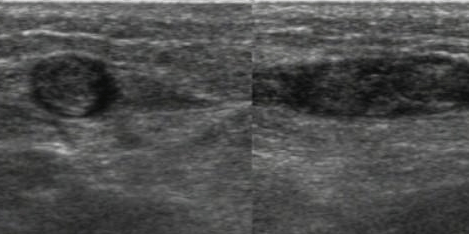

Sai che non sarà facile con tutto quel grasso sottocutaneo che ti aumenta la difficoltà del livello, ma ce la puoi fare. E le visualizzi. Dalla crosse safeno-femorale in giù.

Inizi dalle più interessanti, le vene profonde. Tutte pervie e comprimibili. Poi passi alle superficiali. Visualizzi la crosse safeno femorale e segui la v. grande safena. Due-tre cm dalla crosse, eccolo li. Il trombo. Si estende per almeno 5-6 cm distalmente.

“Operazione compiuta” ti dice il tuo amico ecografo.